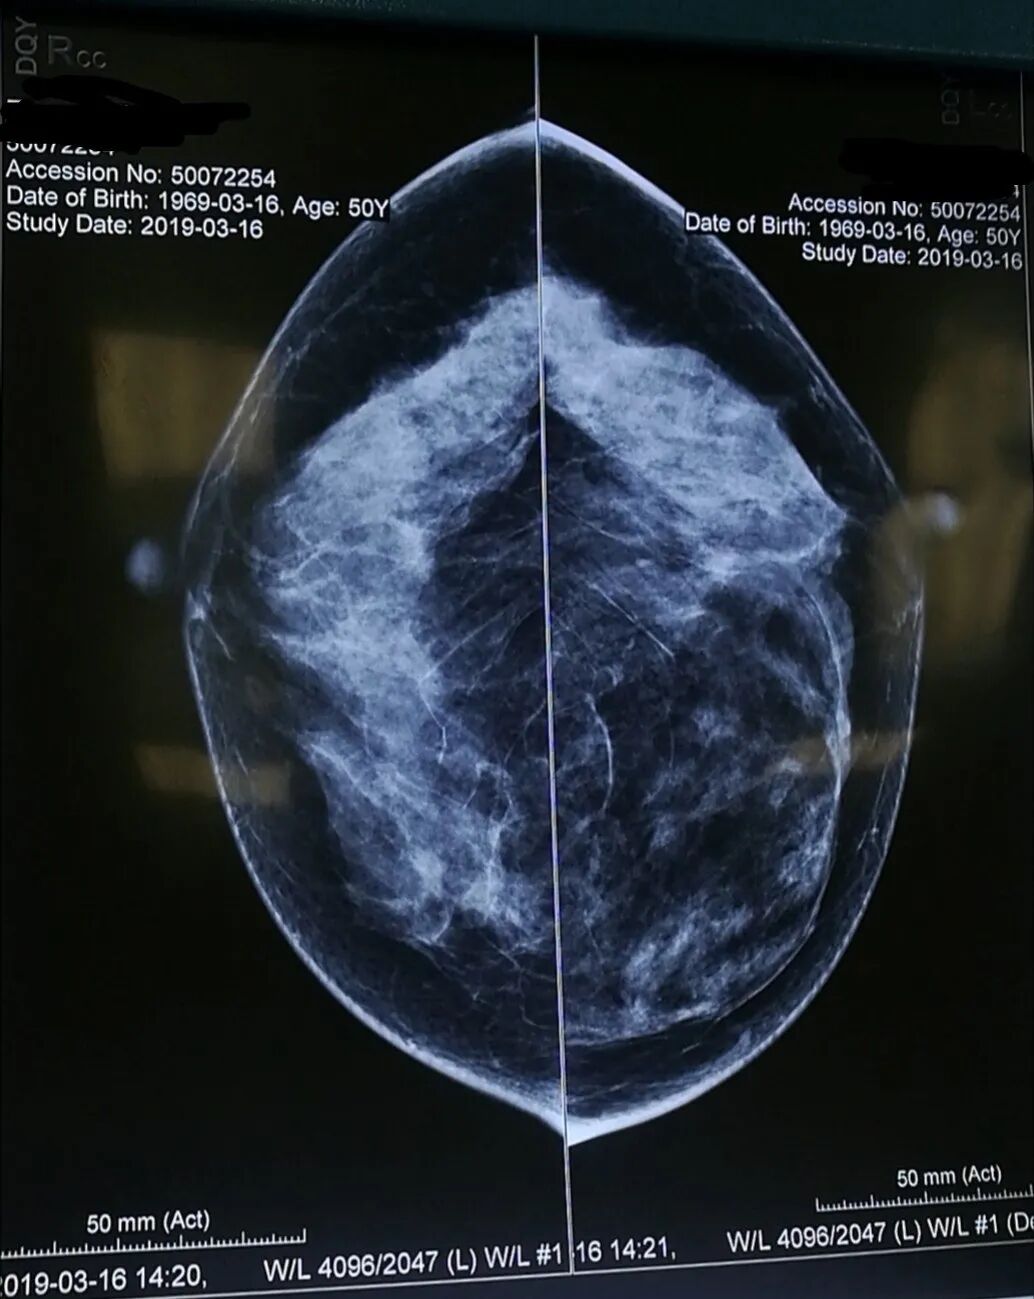

乳腺X线检查是提高乳腺癌早期诊断的主要手段。全数字化平板乳腺机在早期临床诊断乳腺疾病中具有举足轻重的地位。

我院引进德国西门子最新一代全视野数字乳腺机MAMMOMAT Fusion作为乳腺检查的设备, 它采用了人性化设计。具有图像质高,检查舒适、安全、快速的特点,充分体现了对女性患者的关爱。相比其他检查设备,拥有以下明显优点:

3、高效能非晶硅平板探测器,像素尺寸更小,图像更清晰,空间分辨率更高,可满足各种尺寸乳腺的摄影要求,完整显示整个乳腺及腋窝淋巴结部分,避免了漏诊的发生。